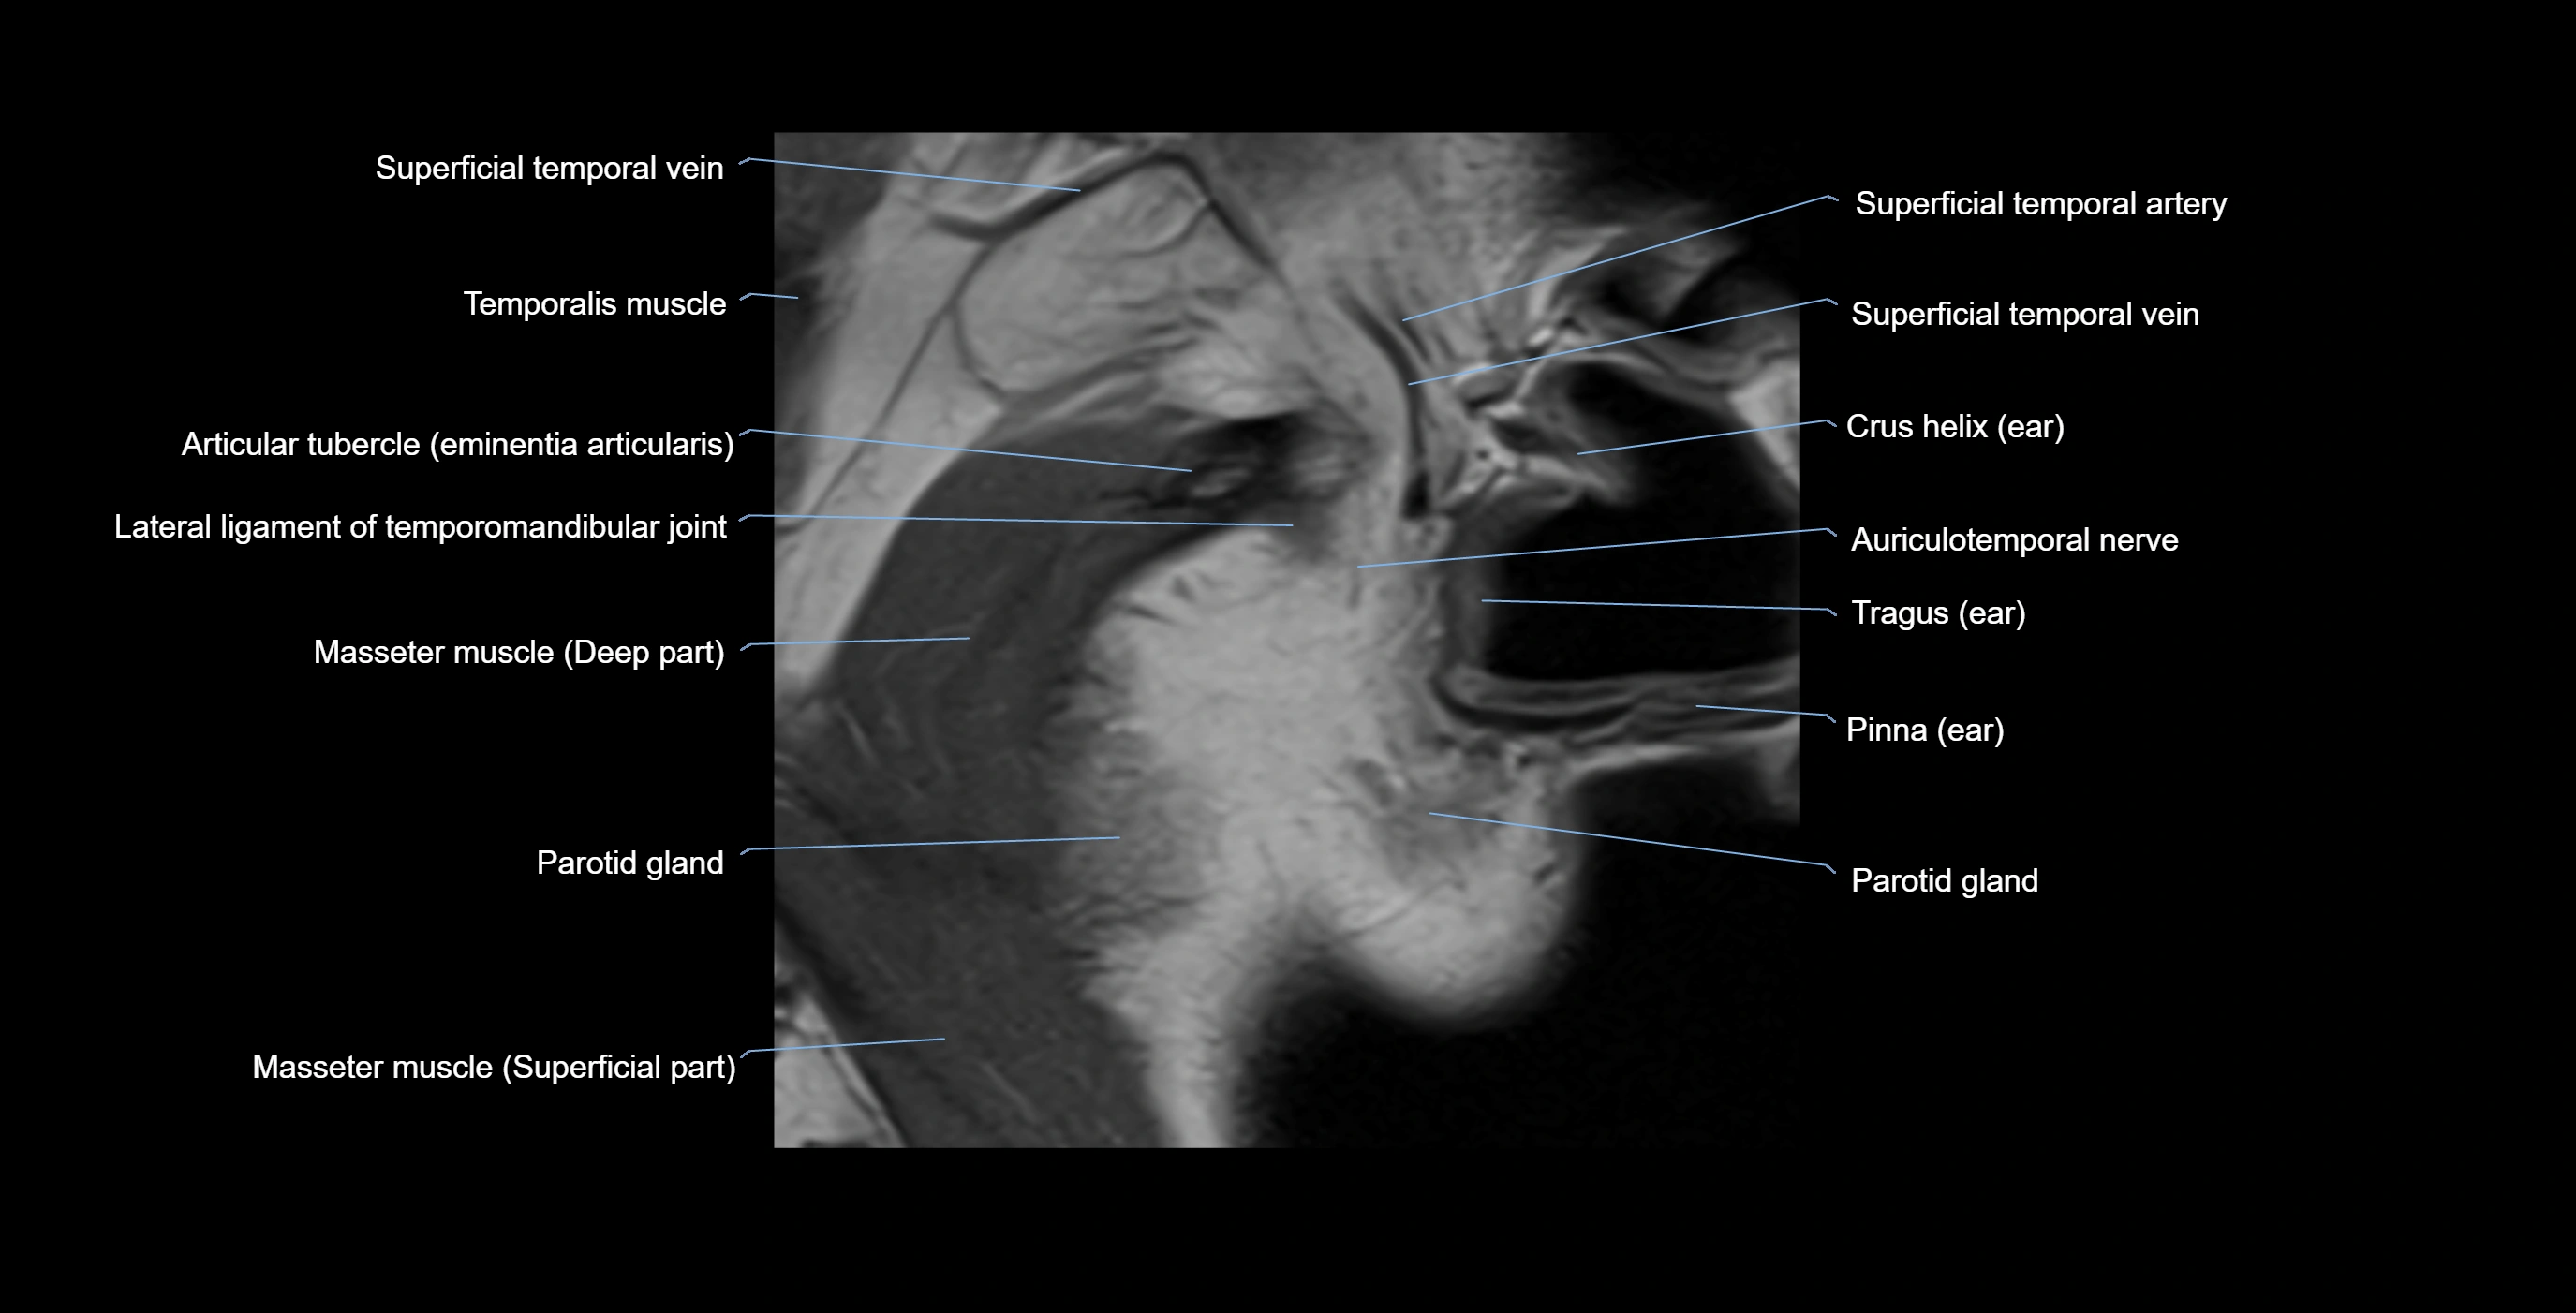

MRI appearance

T1-weighted images:

• Cortical bone: Low signal intensity

• Cancellous marrow: Intermediate to high signal depending on fatty content

• Teeth: Signal void structures

• Adjacent soft tissues: Normal gingiva and oral mucosa signal

T2-weighted images:

• Cortical bone and teeth: Low signal

• Marrow: Intermediate signal